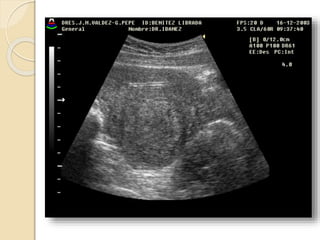

Quistes Endometrósicos:

Clínicamente se manifiesta por dismenorrea,

dispareunia e infertilidad.

La lesion mas detectable por la imágenes esta

constituida por los quistes endometrosicós

(endometriomas) que se forman a partir de los

implantes ováricos configurando los quistes

“achocolatados”.

Se observan quistes de paredes relativamente

gruesas e irregulares con débiles ecos en su

interior debido al contenido hemático.